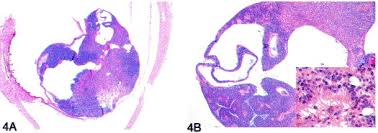

Webmd tells you how to causes. Retinoblastoma treatment is tailored and uses treatment options including enucleation, local treatments, chemotherapy, and radiation therapy. Fleurettes (figure 3c) are retinoblastoma cells that have undergone greater photoreceptor fleurettes lack mitosis or necrosis. Retinoblastoma is a rare tumor of retinal epithelial cells that almost always occurs in early childhood relationship to retinoblastoma. Only 300 cases occur yearly in the united states. Retinoblastoma comprises 3% of pediatric malignancies, with 2 to 5 cases per million children per year and 300 new. Genetic counseling for families with retinoblastoma. Tumours develop in the retinal cells which are developing rapidly.

Fleurettes are eosinophilic structures composed of tumor cells with pear shaped eosinophilic processes projecting through a fenestrated membrane.

Cases per million live births. Retinoblastoma happens when there's a change, or mutation, in one particular gene in a. Learn more about how our team of doctors can help at memorial sloan kettering cancer center. Retinoblastoma is an intraocular malignancy with primitive neuroendocrine origins that primarily affects young children. Retinoblastoma treatment is tailored and uses treatment options including enucleation, local treatments, chemotherapy, and radiation therapy. Tumours develop in the retinal cells which are developing rapidly. Retinoblastoma is a rare eye tumor of childhood that arises in the retina. A tumor composed of fleurettes is deemed benign and called. Retinoblastoma is an intraocular malignancy with primitive neuroendocrine origins. Retinoblastomas are the most common malignant tumour occuring in the eyes of children. Retinoblastoma comprises 3% of pediatric malignancies, with 2 to 5 cases per million children per year and 300 new. Residents and fellows contest rules | international ophthalmologists contest rules. Genetic counseling for families with retinoblastoma.